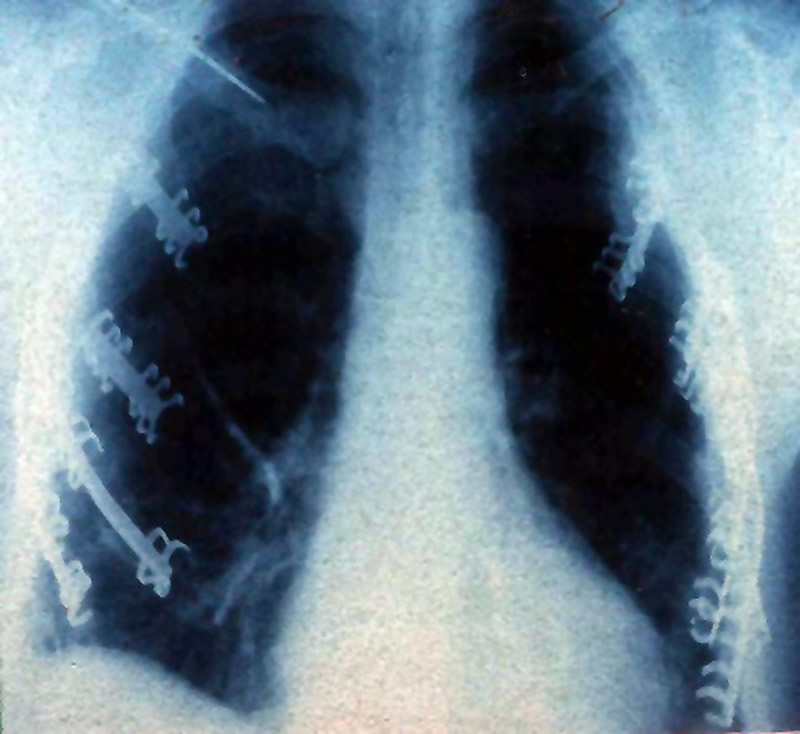

Patients who undergo surgical fixation of a flail chest should be gradually weaned from the ventilator in order to prevent early displacement of the fixed ribs. In our experience mechanical ventilation is usually continued for 36 to 48 hrs postoperatively. The patient is discharged after radiographs (Figure 12) show resolution of traumatic pleuro-pulmonary injuries and after clinical evaluation demonstrates the absence of paradoxical movement of the chest wall. The metal plates do not need to be removed after healing has occurred.